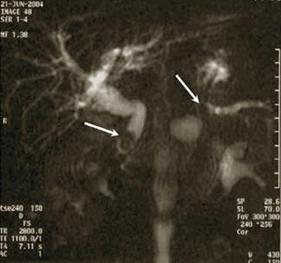

В последние годы широкое распространение приобретает магнитно-резонансная холангиопанкреатография (МРХПГ), обладающая высокой точностью в диагностике причин механической желтухи, особенно в оценке характера и протяженности стриктур желчных путей, а также внутрипротоковых образований. Вместе с тем этот метод лишен пункционно-дренажных лечебных возможностей.

Б

Б – МРТ-изображение холедохолитиаза